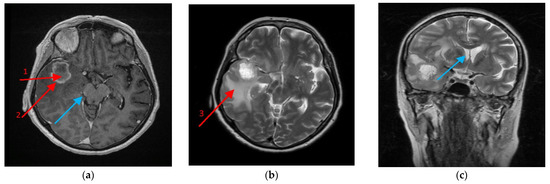

2.1. CCL18 Expression in GBM Tumors Is Elevated Relative to the Peritumoral Area

2.5. Macrophages and CCL18 Expression Are Co-Localized with Each Other in the GBM Tumor